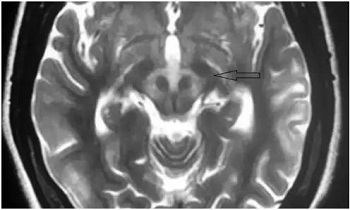

在查房的间隙,贾映海教授便在走廊里继续开讲起“走廊课堂”——“何谓熊猫征”来。贾映海教授说,“熊猫征”主要有“大熊猫脸征”和“小熊猫脸征”。其中,“大熊猫脸征”,红核在T2WI上呈现对称性的低信号,为大熊猫的眼,红核周围的内侧丘系、大脑脚上部、红核脊髓束及皮质脑干束神经纤维受累表现为T2高信号, 构成大熊猫脸上半部白色的轮廓;而双侧上丘、中脑导水管周围灰质神经核团正常的短T2信号及中脑导水管的长T2信号构成了大熊猫脸的下半部。

贾映海教授接着说,“小熊猫脸征”,中脑下部层面的双侧大脑脚、 上丘、 导水管、 导水管周围灰质核团、中央上核等构成了小熊猫脸的大体结构, 而双侧受累而呈长T2 信号的红核周围纤维束与短T2的中央被盖束勾勒出小熊猫的双眼。